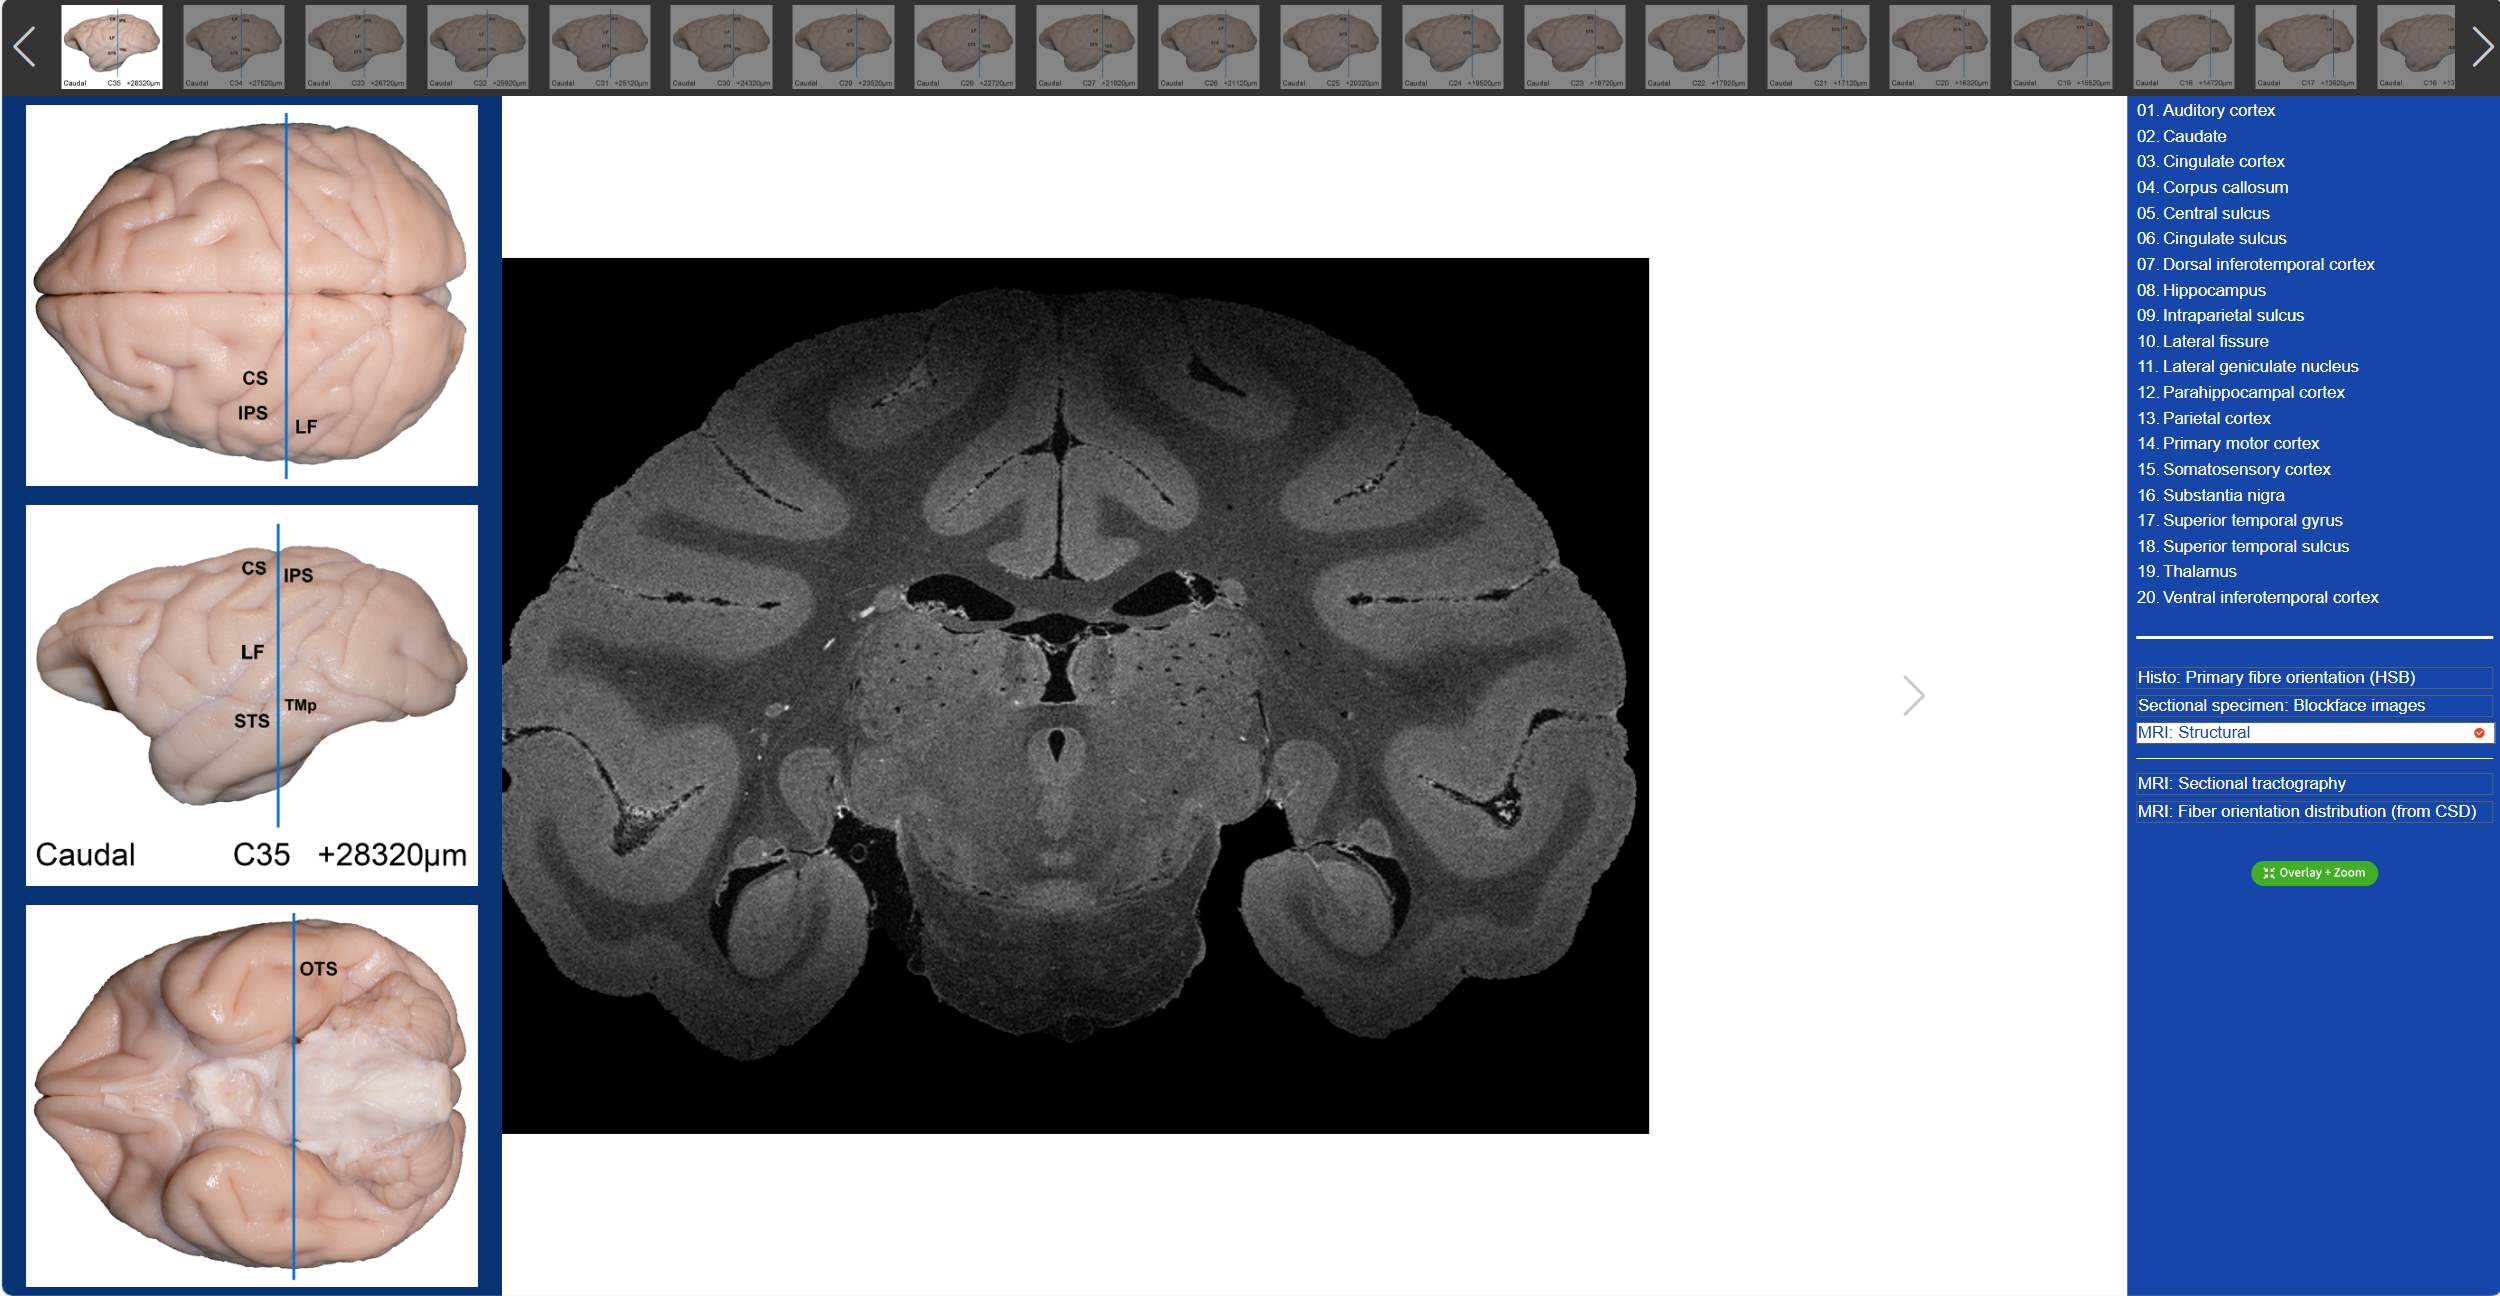

值得一提的是,在“動物腦樂園”里,不僅可以觀察到獼猴3D腦標本,還可以看到獼猴的全腦切片。吳勁松教授團隊從同一猴腦的離體MRI及全腦組織切片髓鞘染色(LFB)數(shù)據(jù)集中,間隔800μm取一層,構建了集合組織切片髓鞘染色(LFB)、組織切片髓鞘染色-偽彩化、斷層標本圖、高分辨率MRI結構像及離體腦dMRI斷層纖維束成像和纖維方向分布圖(限制球面反卷積-CSD)六大模態(tài)的斷層對照圖譜。我們只需要點擊相應的解剖名稱,就可以在圖譜上對應位置顯示標記,同時可與另外兩大模態(tài)的dMRI方向性信息進行對照,極大的方便了我們的觀看。